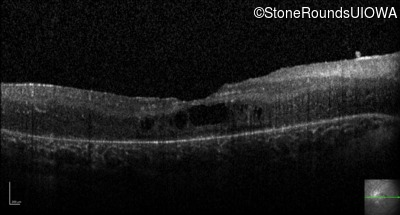

Optical Coherence Tomography - Right - 20/80 -1

Exemplar / OCT Stack